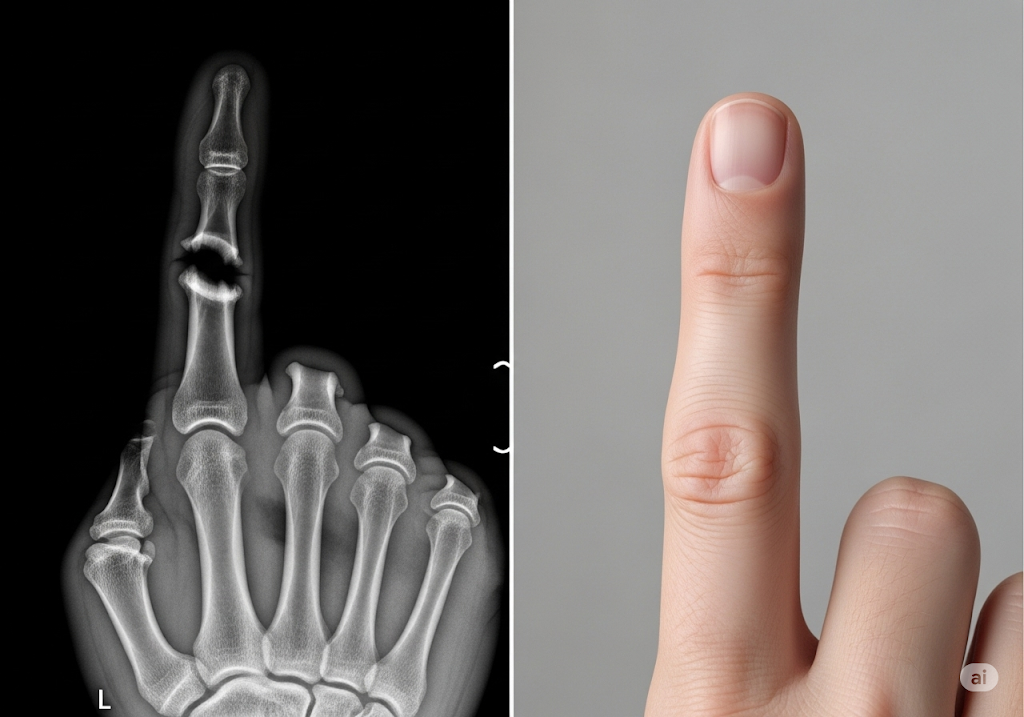

Bone Biologics nộp bằng sáng chế cho protein NELL-1: Bước đột phá trong phẫu thuật cột sống

Bone Biologics, một nhà phát triển các sản phẩm chỉnh hình sinh học tiên tiến, vừa nộp đơn xin cấp bằng sáng chế tại Mỹ cho công nghệ protein NELL-1 của mình. Cách tiếp cận mới lạ này nhằm mục đích cải thiện tỷ lệ thành công của phẫu thuật hợp nhất cột sống và […]